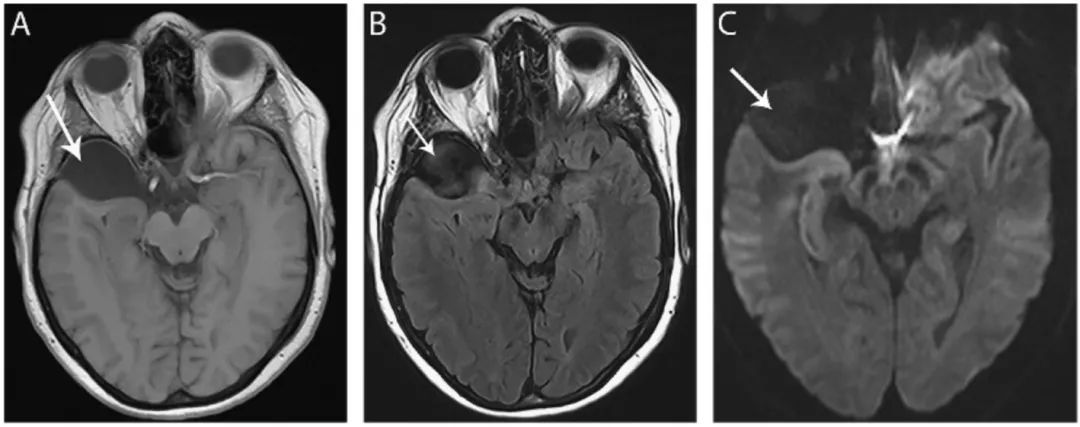

图19 表皮样囊肿

轴位T1 (A)、T2 (B)和FLAIR(C)像显示鞍上区有一个突出的囊肿(箭头),为T1低信号、T2高信号、FLAIR等信号,囊肿引起丘脑的占位效应,引起第三脑室变形(箭头)。DWI像(D)显示囊肿明显高信号(箭头),不同于蛛网膜囊肿。